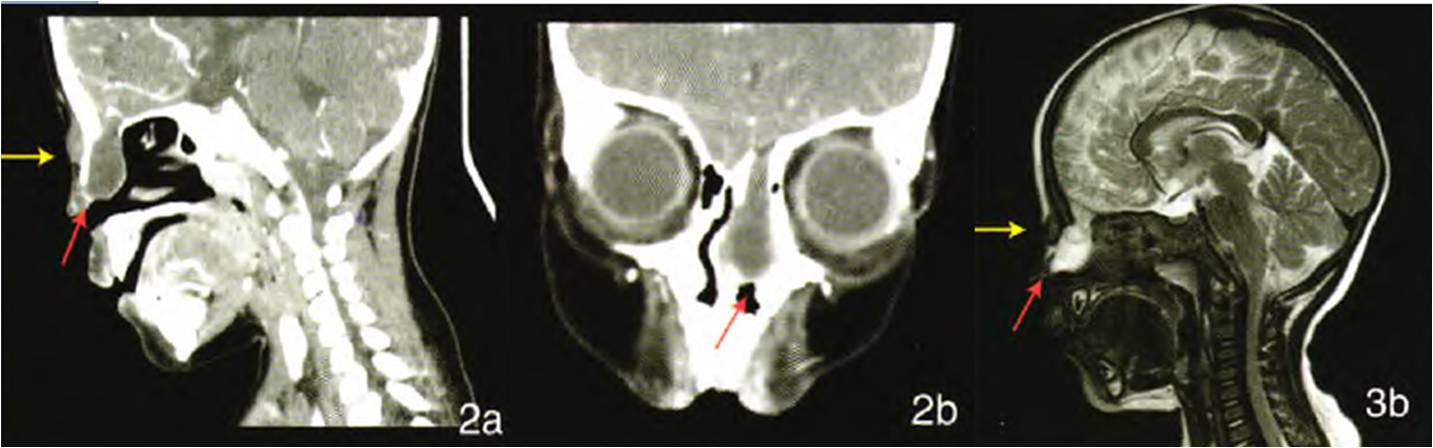

女,2歲,先天性鼻內(nèi)腦膜腦膨出。左側(cè)篩骨水平板缺損,膨出物與顱內(nèi)相同,突入左側(cè)鼻腔內(nèi),左側(cè)鼻中隔受壓移位。